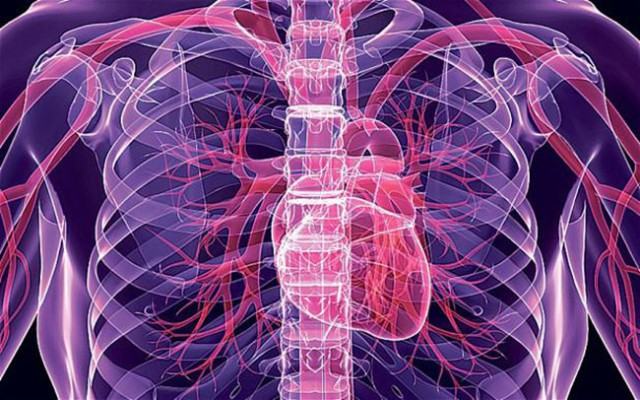

L’eccezionale innovazione si deve anche al dr. Carmine Gentile, nato a Paola e attualmente in forze presso l’Università di Sydney